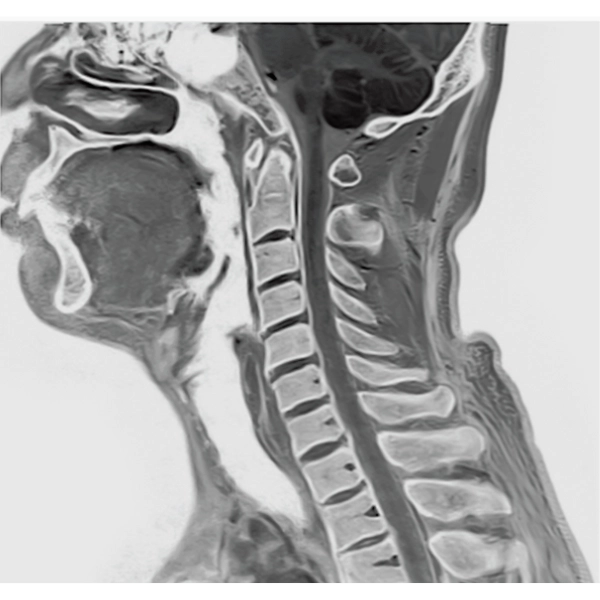

"DLR" is applicable to all body parts and promotes high speed imaging and diagnostic efficiency

IP-RAPID x DLR Plus can also shorten imaging time, allowing more images to be taken in the same examination time.

Additional imaging, such as different image types and cross sections, can be added to the conventional examination to increase the amount of information and make the diagnosis more reliable.

IP-RAPID x DLR Plus gives you the flexibility to shorten respiratory gated series or even replace them with breath-holds, depending on the patient’s situation. This gives you more options and a wider range of examinations to choose from.

IP-RAPID x DLR Plus can be used for basic imaging such as VolumeScan, RadialScan, HalfScan, and many other imaging methods such as MultiContrastScan FatSep and DWI.

It can also be used with time-consuming scans such as Whole Body DWI and Whole Spine imaging, providing more detailed information in many areas than previously possible.